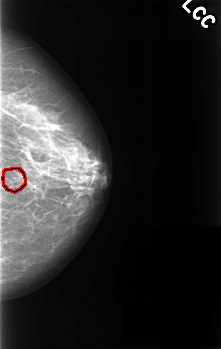

C_0325_1.LEFT_CC

LEFT_CC LINES 4536 PIXELS_PER_LINE 2872 BITS_PER_PIXEL 12 RESOLUTION 50 OVERLAY

FILE: C_0325_1.LEFT_CC.OVERLAY

TOTAL_ABNORMALITIES 1

ABNORMALITY 1

LESION_TYPE CALCIFICATION TYPE PUNCTATE DISTRIBUTION CLUSTERED

ASSESSMENT 4

SUBTLETY 4

PATHOLOGY BENIGN

TOTAL_OUTLINES 1

BOUNDARY